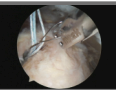

Medical HD Wireless Transmission

Technical Advancements:

1. Uncompressed, lag-free HD wireless image transmission

2. FCC-compliant electromagnetic radiation design and manufacturing

3. FDA-compliant wireless coexistence design and manufacturing

4. FDA 510K-compliant development and production of wireless HD endoscope

systems

5. 510K-compliant network security for firmware and system software development

6. Wireless encrypted control for system communication

Applications:

1. Wireless HD endoscopes in the medical industry

2. Portable forensic endoscopes for autopsy and crime scene investigation

3. Lightweight, self-powered wireless endoscopes for disaster relief and mobile

medical support

William John

Lead Inventor & Total Designer

Chief Technology Development Officer

EL3 Imaging

Developer of the Nuvis-2K Wireless HD Endoscopic Camera System

★ FDA 510(k) Cleared K242606 | November 20, 2025